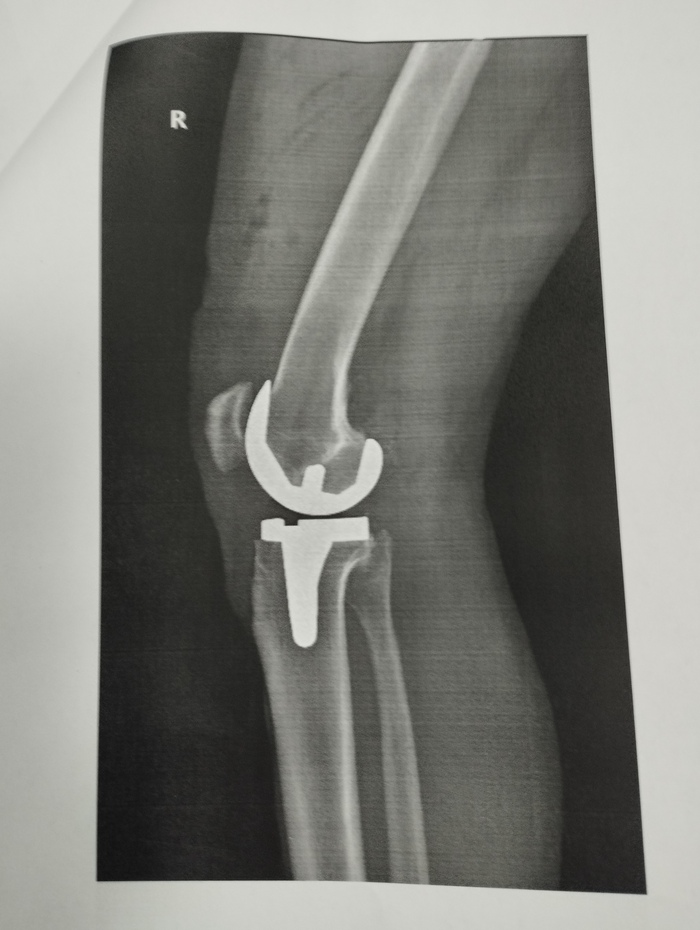

Итак, лет пять-шесть назад начали побаливать коленки, ходил к врачам -ставили артроз. Сначала были таблетки и мази, потом были уколы, в том числе очень дорогущие, которые лично мне особенно никакого улучшения не приносили. В прошлом году делал и уколы собственной плазмой - тоже без эффекта.((( Очень резко ухудшилась ситуация после ковида- такое впечатление, что просто процесс разрушения хряща пошёл лавинообразно. Причём, если в двадцать первом году в левом колене ставили третью степень гонартроза, а в правом вторую, то, к моменту операции, левый сустав как будто не ухудшился, а вот правый прям очень доставлял. Самое главное, что заставило уже не откладывать операцию - в правом колене начались боли независимо от движения, даже в состоянии покоя. Я не мог спать ночью - любое движение приводило к резкой боли, да и без движения были режущие колющие боли.

Почему откладывал операцию до последнего: потому что в двадцать первом году знакомый травмотолог-ортопед сказал, что операция на колене достаточно сложная, так как сустав не простой, шансы на его удачный исход 50/50 и надо пытаться сохранить сустав до последнего. И вот- этот последний момент настал осенью этого года. До этого я много наслушался разных мнений. Но, в основном, сейчас уже все говорили, что операция отработанная, делается во многих местах, а уж в Москве-то вообще практически чуть ли не в каждой больнице. Однако, многие рекомендовали больницу №13 на Велозаводской,(сейчас она филиал №1 больницы им. Демихова), так как там самая старая школа эндопротезирования, поэтому, когда предлагали куда пойти, выбрал её. Раньше такие операции, поскольку они дорогостоящие, и делаются по квоте, надо было ждать продолжительное время. Сейчас ждать практически не приходится, ну -месяц, за это время сдаёшь необходимые анализы и в назначенный день приходишь в больницу. С собой берёшь обычный больничный набор, плюс костыли и эластичные бинты для бинтования ног от тромбов. Единственное - вместо штанов на время госпитализации надо брать шорты! Это важно. Ещё наденьте свободную обувь и возьмите какую-нибудь обувную ложку, чтобы было проще одеваться, когда будете уезжать домой. Не могу сказать что я сильно мандражировал - наверное с возрастом как-то всё притупляется (мне 59). К тому же мне необходимо быть на ногах и нормально ходить, да и измучился. Набор анализов не очень большой- кстати, даже не делали ПЦР на ковид, который, насколько я знаю, до последнего времени при операциях был обязателен. Должны были меня положить в среду утром и днём прооперировать. Но, во вторник позвонили и сказали: если сможете приехать сегодня вечером, то прооперируем вас завтра рано с утра, первым. Я, конечно, согласился, быстро собрался и полетел. На следующий день в 8:00 утра уже лежал голенький в операционной. Очень много я начитался в этих ваших интернетах про операцию, в том числе про то что наркоз не общий, а эпидуральный и, чтобы не слышать как со мной проводят всю экзекуцию, попросил анестезиолога добавить к эпидуралке мне седацию -это когда ты просто спишь во время операции. Ещё важный момент (я сталкивался с этим раньше, когда делал операцию по ушиванию грыжи) - попросил, чтобы мне поставили мочевой катетер, так как первые сутки ты лежишь, а писать очень хочется, в том числе и из-за того что ставят капельницы. И вот тут катетер- это просто какое-то неземное спасение- ты просто не испытываешь позывов в мочеиспусканию, всё само выливается, в противном случае вся процедура с уткой непростая да и двигаться больно. Пока сёстры готовили операционную, побалагурил с ними, потом пришли врачи - укольчик в спину, маску, и я провалился. Но даже сквозь этот медикаментозный сон я слышал, как в меня как будто кувалдой вбивали эти протезы. Кстати о протезах. Много слышал разных мнений о протезах: и то что есть хорошие, но за них надо доплачивать, есть - не ахти, поэтому специально поинтересовался у врача как сейчас обстоит дело. Информация такая: в Москве либо ты делаешь операцию полностью платно, и тогда можешь выбирать протезы любые, в том числе и супер-пупер импортные, по параллельному импорту. Либо ты делаешь по полису, и тогда тебе ставят то, что есть в больнице. Мне сказали, что сейчас в больнице используют китайские протезы, они полные аналоги американских, и считаются хорошего качества. Как сказал врач: во всяком случае лучше отечественных. Итак, после операции привезли в палату, где я часок находился в полусне, потом начал приходить в себя. Очень интересные ощущения от эпидуралки: ты просто не чувствуешь нижней половиной тела, не можешь двигать ногами и, даже, в какой-то момент становится слегка тревожно: блин, а вдруг что-то не так и теперь не сможешь двигаться ... Но, часа через три, начинаешь двигать пальцами ног, а потом полностью возвращается чувствительность. Единственное- нет боли, так как, во-первых, ставят блокаду, а во-вторых, колят обезбол. Конечно нелегко лежать когда не можешь никуда повернуться - очень устаёт спина и всё тело. Через часов 12 отходит блокада и становится больно, но вызываешь сестру -тебе делают укол и боль снимает. Первый обезбол после операции колят промедол, это синтетический аналог морфина, остальные дни уже не наркотик а кеторолак, но тоже хорошо снимает боль. На следующий день после операции (через сутки) снимают мочевой катетер, делают перевязку. Приходит врач-реабилитолог - дают инструкцию ЛФК и уже надо начинать заниматься разработкой ноги. Уже начинаешь вставать и сам костыляешь в туалет. Ещё одно важное замечание - обязательно надо взять с собой влажные салфетки, потому что весь туалет и гигиена происходит с их помощью. Итак, с самого начала врачи говорят, что можно и даже нужно на ногу наступать, а костыли только дозируют нагрузку и дают поддержку. Дело в том, что протезы ставятся на специальный костный цемент, плюс они же с шипами и забиваются в сустав и практически сразу намертво там фиксируются. И действительно - ты достаточно спокойно можешь на эту ногу наступать - боли в суставе нет вообще, - вся боль только от того, что всё-таки делали большой разрез, всё там раскрывали, резали, пилили. Конечно повреждения мягких тканей значительные, и нога очень отёкшая и всё это болит. Точнее, благодаря обезболу не болит, а просто ею пока двигать больно. Именно когда пытаешься её сгибать или поворачивать. Возвращаясь к протезу: там же меняется не весь сустав, а просто спиливают с него верхнюю часть, где был хрящ, и вот туда ставят протез: на картинке видно какой. В общем, уже со второго дня я достаточно бодренько костылял по всему отделению, и даже спускался по лестнице вниз, в приёмное, где стоял кофейный аппарат. Кстати, ходьба по лестнице, входит в программу ЛФК со второго дня. По лекарствам: по сути, кроме обезбола больше ничего не делали. Я удивился, что не стали колоть никаких антибиотиков, наверное это делают если поднимается температура, это означает, что пошло какое-то воспаление . У меня всё было нормально, поэтому мне только кололи обезбол, давали омепразол для желудка и кроверазжижающее. Кстати, обязательно настаивают на том, чтобы компрессионные чулки (или в моём случае эластичные бинты) носились не меньше месяца, и в это же время принимать надо кроверазжижающее, во избежание тромбоза нижних конечностей. Я знаю, что обычно этим все пренебрегают, я постараюсь максимально следовать этому указанию, хотя конечно бинты давят, и это один из неприятнейших моментов послеоперационного периода. Буду заканчивать - уже сам устал писать эту простыню! Выписали меня на следующий понедельник утром, сделав последнюю перевязку и дав выписку и рекомендации. В больницу и обратно свозил меня друг на машине. Дома потихоньку восстанавливаюсь, чуть полегче стало примерно через день: чуть чуть начал спадать отёк и синяк, ну и вообще - дома стены лечат. Но пока нога гнётся очень мало, но делаю упражнения. Мне надо поскорее встать на ноги - мне очень важно ездить на машине. Врачи сказали что через 2.5 - 3 недели, в общем, на машине с коробкой автоматом ездить можно. А вообще, на костылях ходишь полтора месяца, а потом просто ходишь с палочкой месяц. Считается, что через 3 месяца ты абсолютно здоров, а полгода - это вообще абсолютно полная реабилитация. Посмотрю как дела пойдут дальше, - если всё будет хорошо, то через 3-4 месяца сделал бы и вторую ногу, которая тоже в очень плохом состоянии. Спасибо за внимание тем кто осилил, закончен репортаж!))) Если есть вопросы -задавайте, постараюсь ответить. Но, как говорил, не могу делать это часто и быстро.